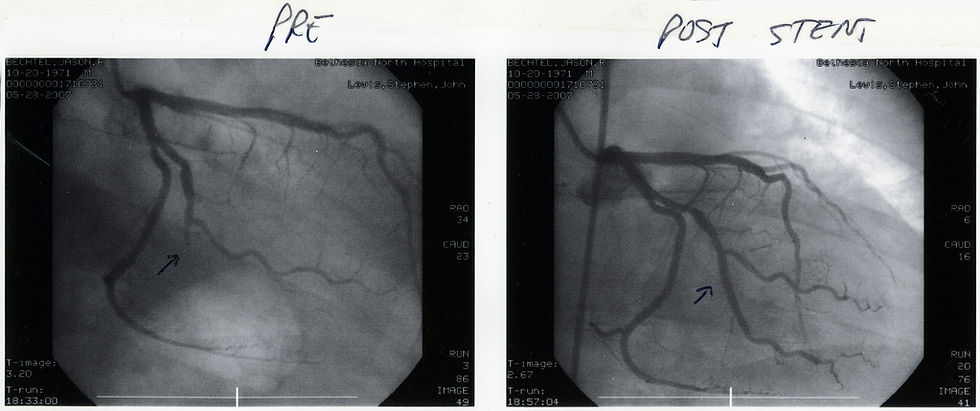

Uzun süren ve tekrarlayan göğüs ağrısı olan kişilerde, instabil angina (UA) denen bir durum veya non-ST elevasyonlu miyokart enfarktüsü (NSTEMI) denen bir tip kalp krizi olabilir. Bu iki durumdan birinde olan hastalara iki tedavi stratejisinden biri uygulanır: Rutin invazif strateji veya konservatif strateji (seçici invazif strateji). İlk yaklaşımda hastaların kalp kasını besleyen koroner damarlara kateterle girilerek koroner anjiyografi ile damarlar görüntülenir. Eğer ciddi bir daralma ya da komplikasyonlu plak görülürse daralan yerde damar balonla genişletilerek bozulan kan akımı iyileştirilir. Sonra yerleştirilen bir metal stentle damarın açık kalması sağlanır. Bazı vak'alarda daralan bölge bu yaklaşıma cevap vermez ve baypas yapmak için cerrahi gerekir.